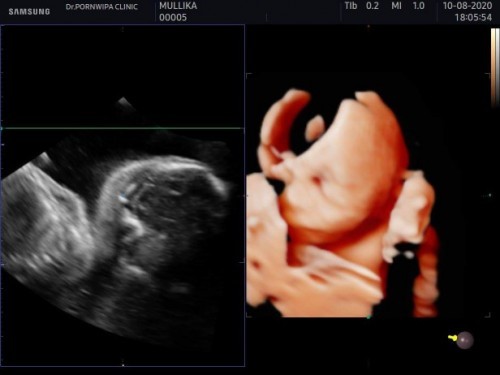

แม่อยากเห็นหน้าลงทุนไปซาว 4 มิติ แต่น้องเอามือปิดหน้าเก่งมาก ชัดสุดได้แค่นี้เอง ทีมธันวามาอวดลูกกันหน่อยค่ะ 😊😊💙💙🤰🤰